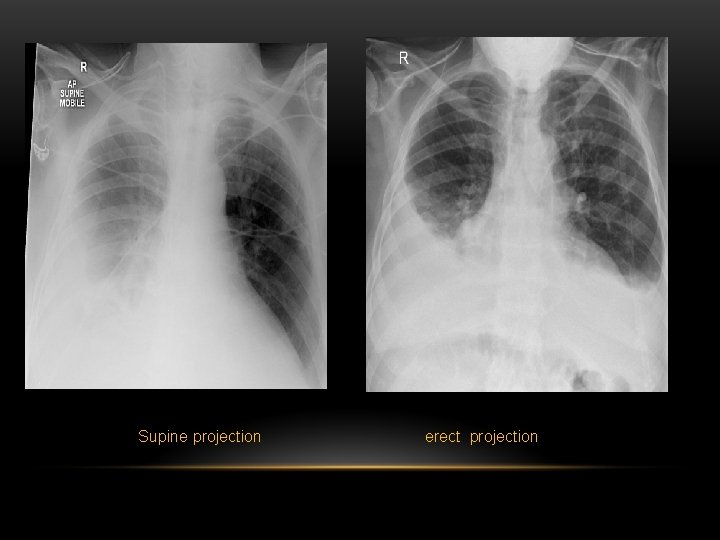

Pleural Effusion Fluid accumulates in the pleural space. Irrespective of the nature of fluid, radiologically they will look similar. Radiological criteria are: Density In dependent portion (Costophrenic angle in PA view). Blunting of costophrenic angle Lack of identifiable diaphragm (silhouette sign principle).

Pleural Effusion • Homogenous density • Loss of cardiophrenic angle • Loss of diaphragmatic and right cardiac silhouette

Supine projection erect projection